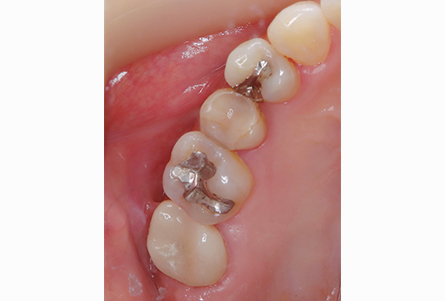

奥歯のジルコニア

| 年齢・性別 | 22歳・男性 |

|---|---|

| 主訴・治療部位 | 他院で虫歯治療 詰め物の治療が必要と判断を受けたが、自費診療の費用が高価で治療を断念 インターネットで当院を知りご来院 右上6番、右上4番 |

| 治療費用 | 合計:88,000円 ジルコニア:44,000円×2 (2023年1月現在) |

| 治療期間 | 約1ヵ月 |

| 治療内容 | 虫歯を除去し、型をとりました。 神経の近くまで虫歯になっていたため、神経の保護処置も行いました。 |

| リスク・副作用 | 虫歯が進行し、神経の治療になる可能性があります。 神経の近くまで削っているため、治療直後は敏感になり痛みが出る可能性があります。 かみ合わせの強い方は詰め物が取れてしまう可能性があります。 |

| 治療方針 | 治療必要な箇所は終了 親知らずは埋まっているが、痛みや腫れはないため、定期検診にて経過観察していきます。 |

| 担当者所見 | 歯周病検査は異常なし 虫歯リスクを下げるため、歯ブラシの他にフロスや歯間ブラシの併用を提案しました。 |